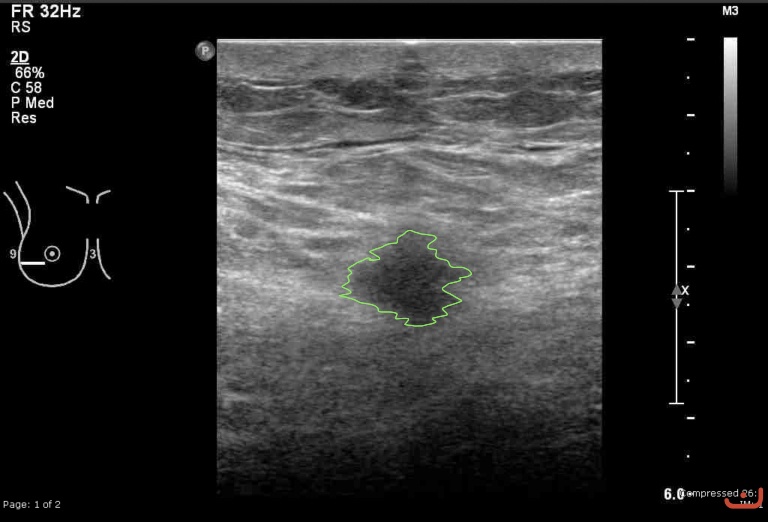

Case 12-G1

Malignant solid mass